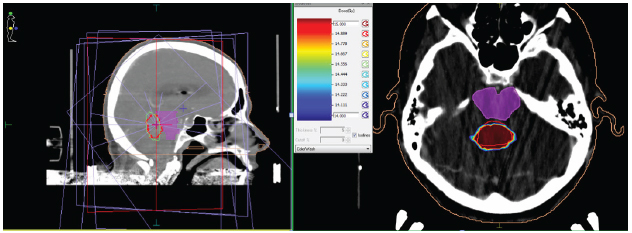

Bajo estos hallazgos se considera que la paciente requiere ser llevada a tratamiento de carácter urgente con radiocirugía de dosis única, dado el sitio donde se ubicó la lesión (en el vermis cerebeloso en íntimo contacto con el acueducto de Silvio) y la aparición de hidrocefalia supratentorial (figuras 2 y 3).